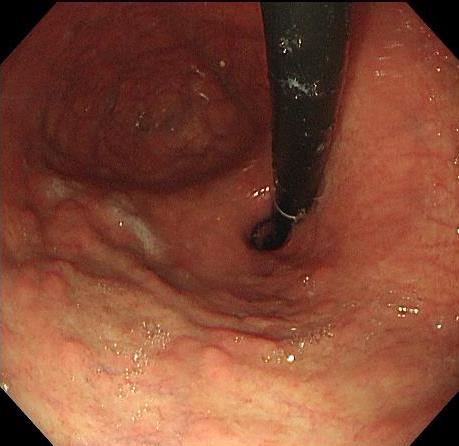

• 利那洛肽联合西甲硅油与复方聚乙二醇电解质散对便秘患者肠道清洁效果的影响

2025, 31(6):44-53. DOI: 10.12235/E20240604

摘要 (241) HTML (93) PDF 1.85 M (139) 评论 (0) 收藏

摘要:目的 探讨利那洛肽联合西甲硅油与复方聚乙二醇电解质散(PEG)对便秘患者肠道清洁效果的有效性和安全性。方法 采用前瞻性随机对照试验,通过单盲法,纳入2023年4月-2024年8月于该院消化内镜中心行结肠镜检查的便秘患者383例,随机分为常规组(128例)、实验A组(128例)和实验B组(127例)。常规组采用3 L PEG(Ⅰ)溶液,实验A组采用290 μg利那洛肽 + 2 L PEG溶液,实验B组采用290 μg利那洛肽 + 30 mL西甲硅油+2 L PEG溶液。比较3组患者的肠道准备效果[Boston肠道准备量表(BBPS)评分和去泡效果]、病变检出率、首次排便间隔时间、排便次数、盲肠插管成功率、进镜时间、退镜时间、不良反应发生率和重复检查意愿等。结果 3组患者BBPS评分比较,差异无统计学意义(P > 0.05);实验B组的去泡效果评分明显低于常规组和实验A组,差异均有统计学意义(P < 0.05);实验B组的病变总检出率和息肉检出率明显高于常规组和实验A组,差异均有统计学意义(P < 0.05);常规组的首次排便间隔时间明显长于实验A组和实验B组,差异均有统计学意义(P < 0.05);3组患者排便次数比较,差异无统计学意义(P > 0.05);3组患者盲肠插管成功率均为100.0%,进镜时间相当,差异均无统计学意义(P > 0.05);实验B组的退镜时间明显短于常规组和实验A组,差异均有统计学意义(P < 0.05);常规组腹胀腹痛发生率和不良反应总发生率明显高于实验A组和实验B组,差异均有统计学意义(P < 0.05);常规组重复检查意愿率明显低于实验A组和实验B组,差异均有统计学意义(P < 0.05)。结论 290 μg利那洛肽联合30 mL西甲硅油与2 L PEG溶液方案在便秘患者肠道准备上具有优势,较3 L PEG溶液和290 μg利那洛肽+2 L PEG溶液方案,可获得更好的肠道清洁效果,且安全性和患者重复检查意愿率高,可作为便秘患者肠道准备的推荐方案。